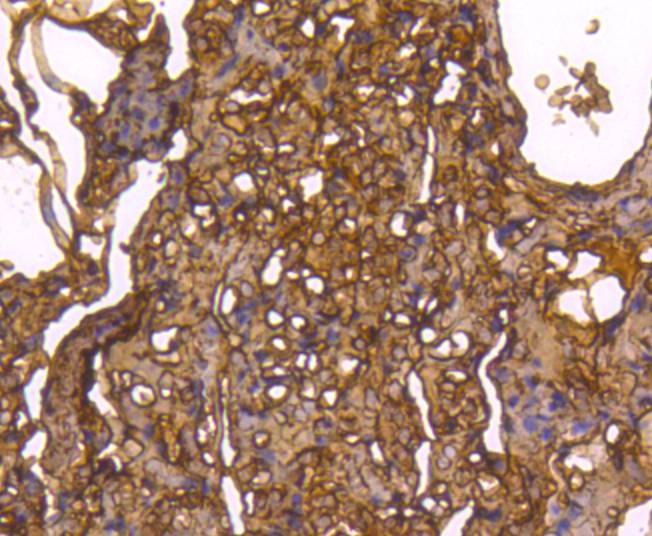

Immunohistochemical analysis of paraffin-embedded human lung tissue using anti-Caspase-1 antibody. Counter stained with hematoxylin.

Immunohistochemical analysis of paraffin-embedded human lung cancer tissue using anti-Caspase-1 antibody. Counter stained with hematoxylin.